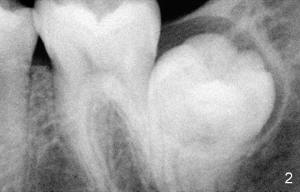

Impacted Lower 2nd Molar

Xin Wei, DDS, PhD, MS 1st edition 09/07/2011, last revision 09/07/2011